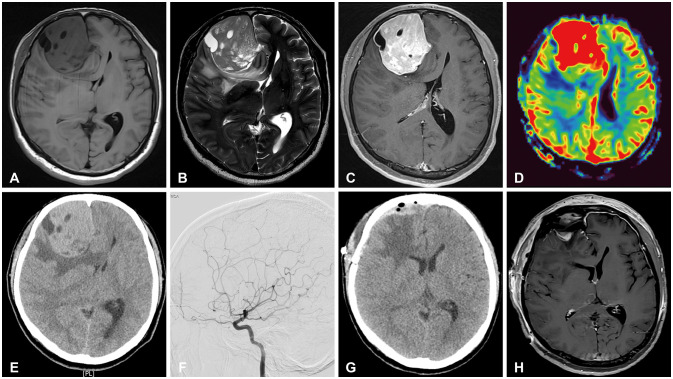

Primary extraosseous intracranial Ewing sarcoma (ES) is an extremely rare disease, limited to the pediatric population, that primarily originates in the skull. Here, we present an unusual case of adult Ewing's sarcoma originating from the brain parenchyma. The 50-year-old male patient visited our hospital with severe headache lasting 3 weeks. MRI presented 6.1×6.2×5.2 cm sized heterogeneously enhanced mass containing peritumoral edema in the right frontal lobe. The patient underwent right frontal craniotomy, at which time the gray and red masses adhered to the surrounding brain parenchyma. The mass was completely resected using neuronavigation and electrophysiological monitoring. Histopathological examination revealed ES-compatible findings of small round cell tumor and CD-99 positive membranous immunostaining. Next generation sequencing revealed translocation and fusion of EWSR1 and FLI1, consistent with a confirmed diagnosis of ES. Consequently, the patient underwent postoperative radiotherapy. The present case revealed adult primary intracranial ES arising from the frontal lobe. Although its etiology remains poorly understood, intraparenchymal ES should be included in the differential diagnosis of parenchymal brain tumors.